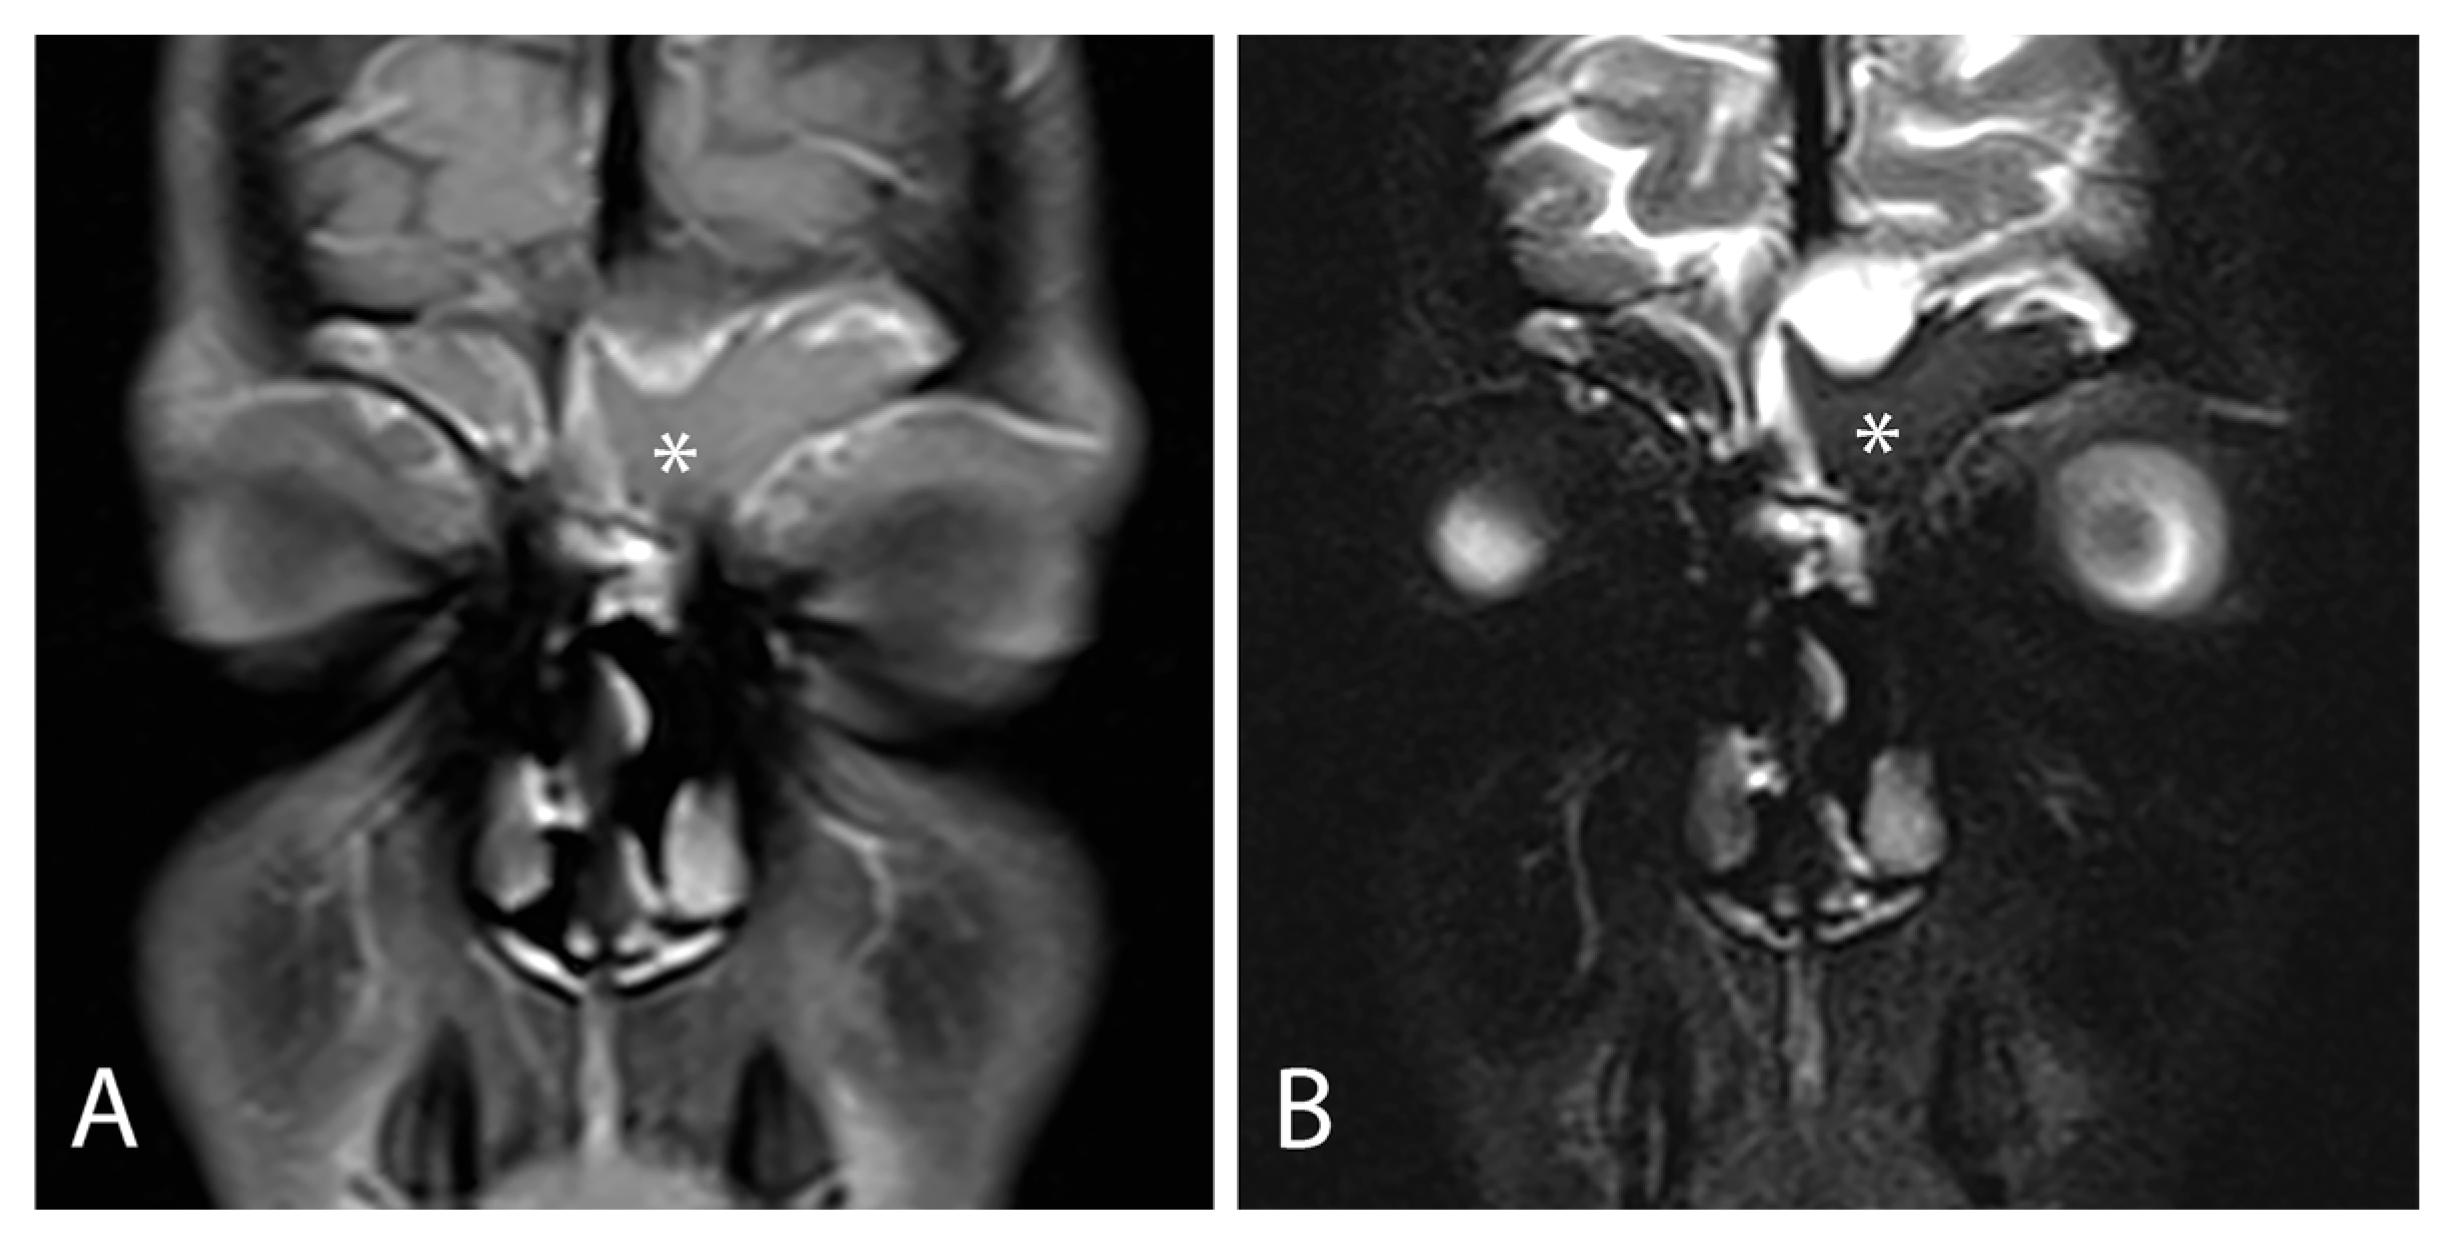

| Sinonasal Nasal obstruction (81.1%) (unilateral or bilateral) Rhinorrhea (50%) Hyposmia or anosmia (27%) Headache (50%) Facial pain Ocular Epiphora Exophtalmia Hyperemic conjunctive Others Mouth breathing Chronic cough Throat clearing Halitosis Activity intolerance Agitated or restless sleep Snoring Sleep apnea Failure to thrive | Nasal mucosa congestion, particularly with turbinates Prominent uncinate process Bulging of lateral wall (unilateral or bilateral) Nasal polyps (33–56.5%) Septal deformity Choanal stenosis Viscous and/or purulent nasal secretions Adenoid hypertrophy Cobblestoning of posterior pharynx | CT Opacification of the sinus (hourglass image) Mucocele Bulging or displacement of lateral nasal wall Demineralization of uncinate process Hypoplasia or aplasia of the paranasal sinuses Inverse relationship between the size of anterior and posterior ethmoid sinus Decreased pneumatization of the sinus MRI Mucosal swelling Mucopyoceles Polyps Maxillary sinus wall deformation Delay pneumatization | Bacteria Pseudomonas aeruginosa Staphylococcus aureus Haemophilus influenzae Streptococcus species Achromobacter xylosoxidans Fungi Candida albicans Aspergillus fumigatus Exserophilum species Penicillum species |